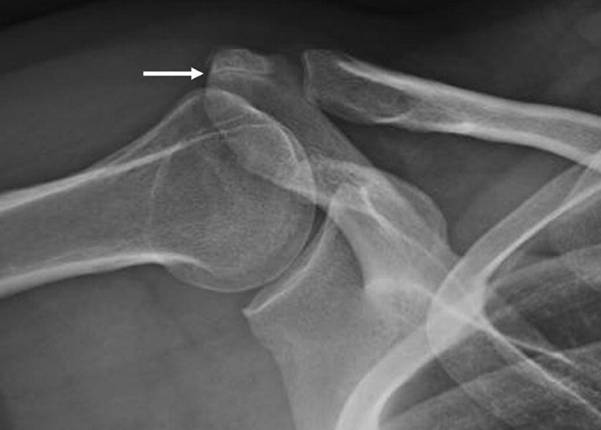

Diagnosing OsAcromiale typically involves imaging studies:

- Radiographs: The best initial imaging technique is an axillary lateral X-ray of the shoulder, which can clearly reveal the unfused fragment.